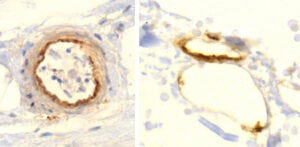

9. Endothelial stripping and destruction of a small blood vessel after vaccination

We now turn to the evidence of immune attack on the endothelial cells which produce the spike protein. On the left, a normal venule, delimited by an intact endothelium and containing some red blood cells and few white blood cells (stained blue) inside.

The image on at the centre shows a venule that is being attacked and destroyed by the immune system. The outline is already dissolving, and the spindle-shaped (and swollen) endothelial cells have peeled off from the vessel wall. Furthermore, we see lymphocytes—the small cells with dark, round nuclei and with very little cytoplasm around them; a single lymphocyte (at much higher magnification) is shown on the right.

Lymphocytes are the backbone of the specific immune system—whenever antigens are recognized and antibodies are produced, this is done by lymphocytes. Also among the lymphocytes we find cytotoxic T cells and natural killer cells, which serve to kill virus-infected cells—or ones that look to them as if infected, because they have been forced to produce a viral protein by a so-called vaccine.

A crucial function of the endothelium is to prevent blood clotting. Thus, if the endothelium is damaged, as it is in this picture, and the tissues beyond it make contact with the blood, this will automatically set off blood clotting.